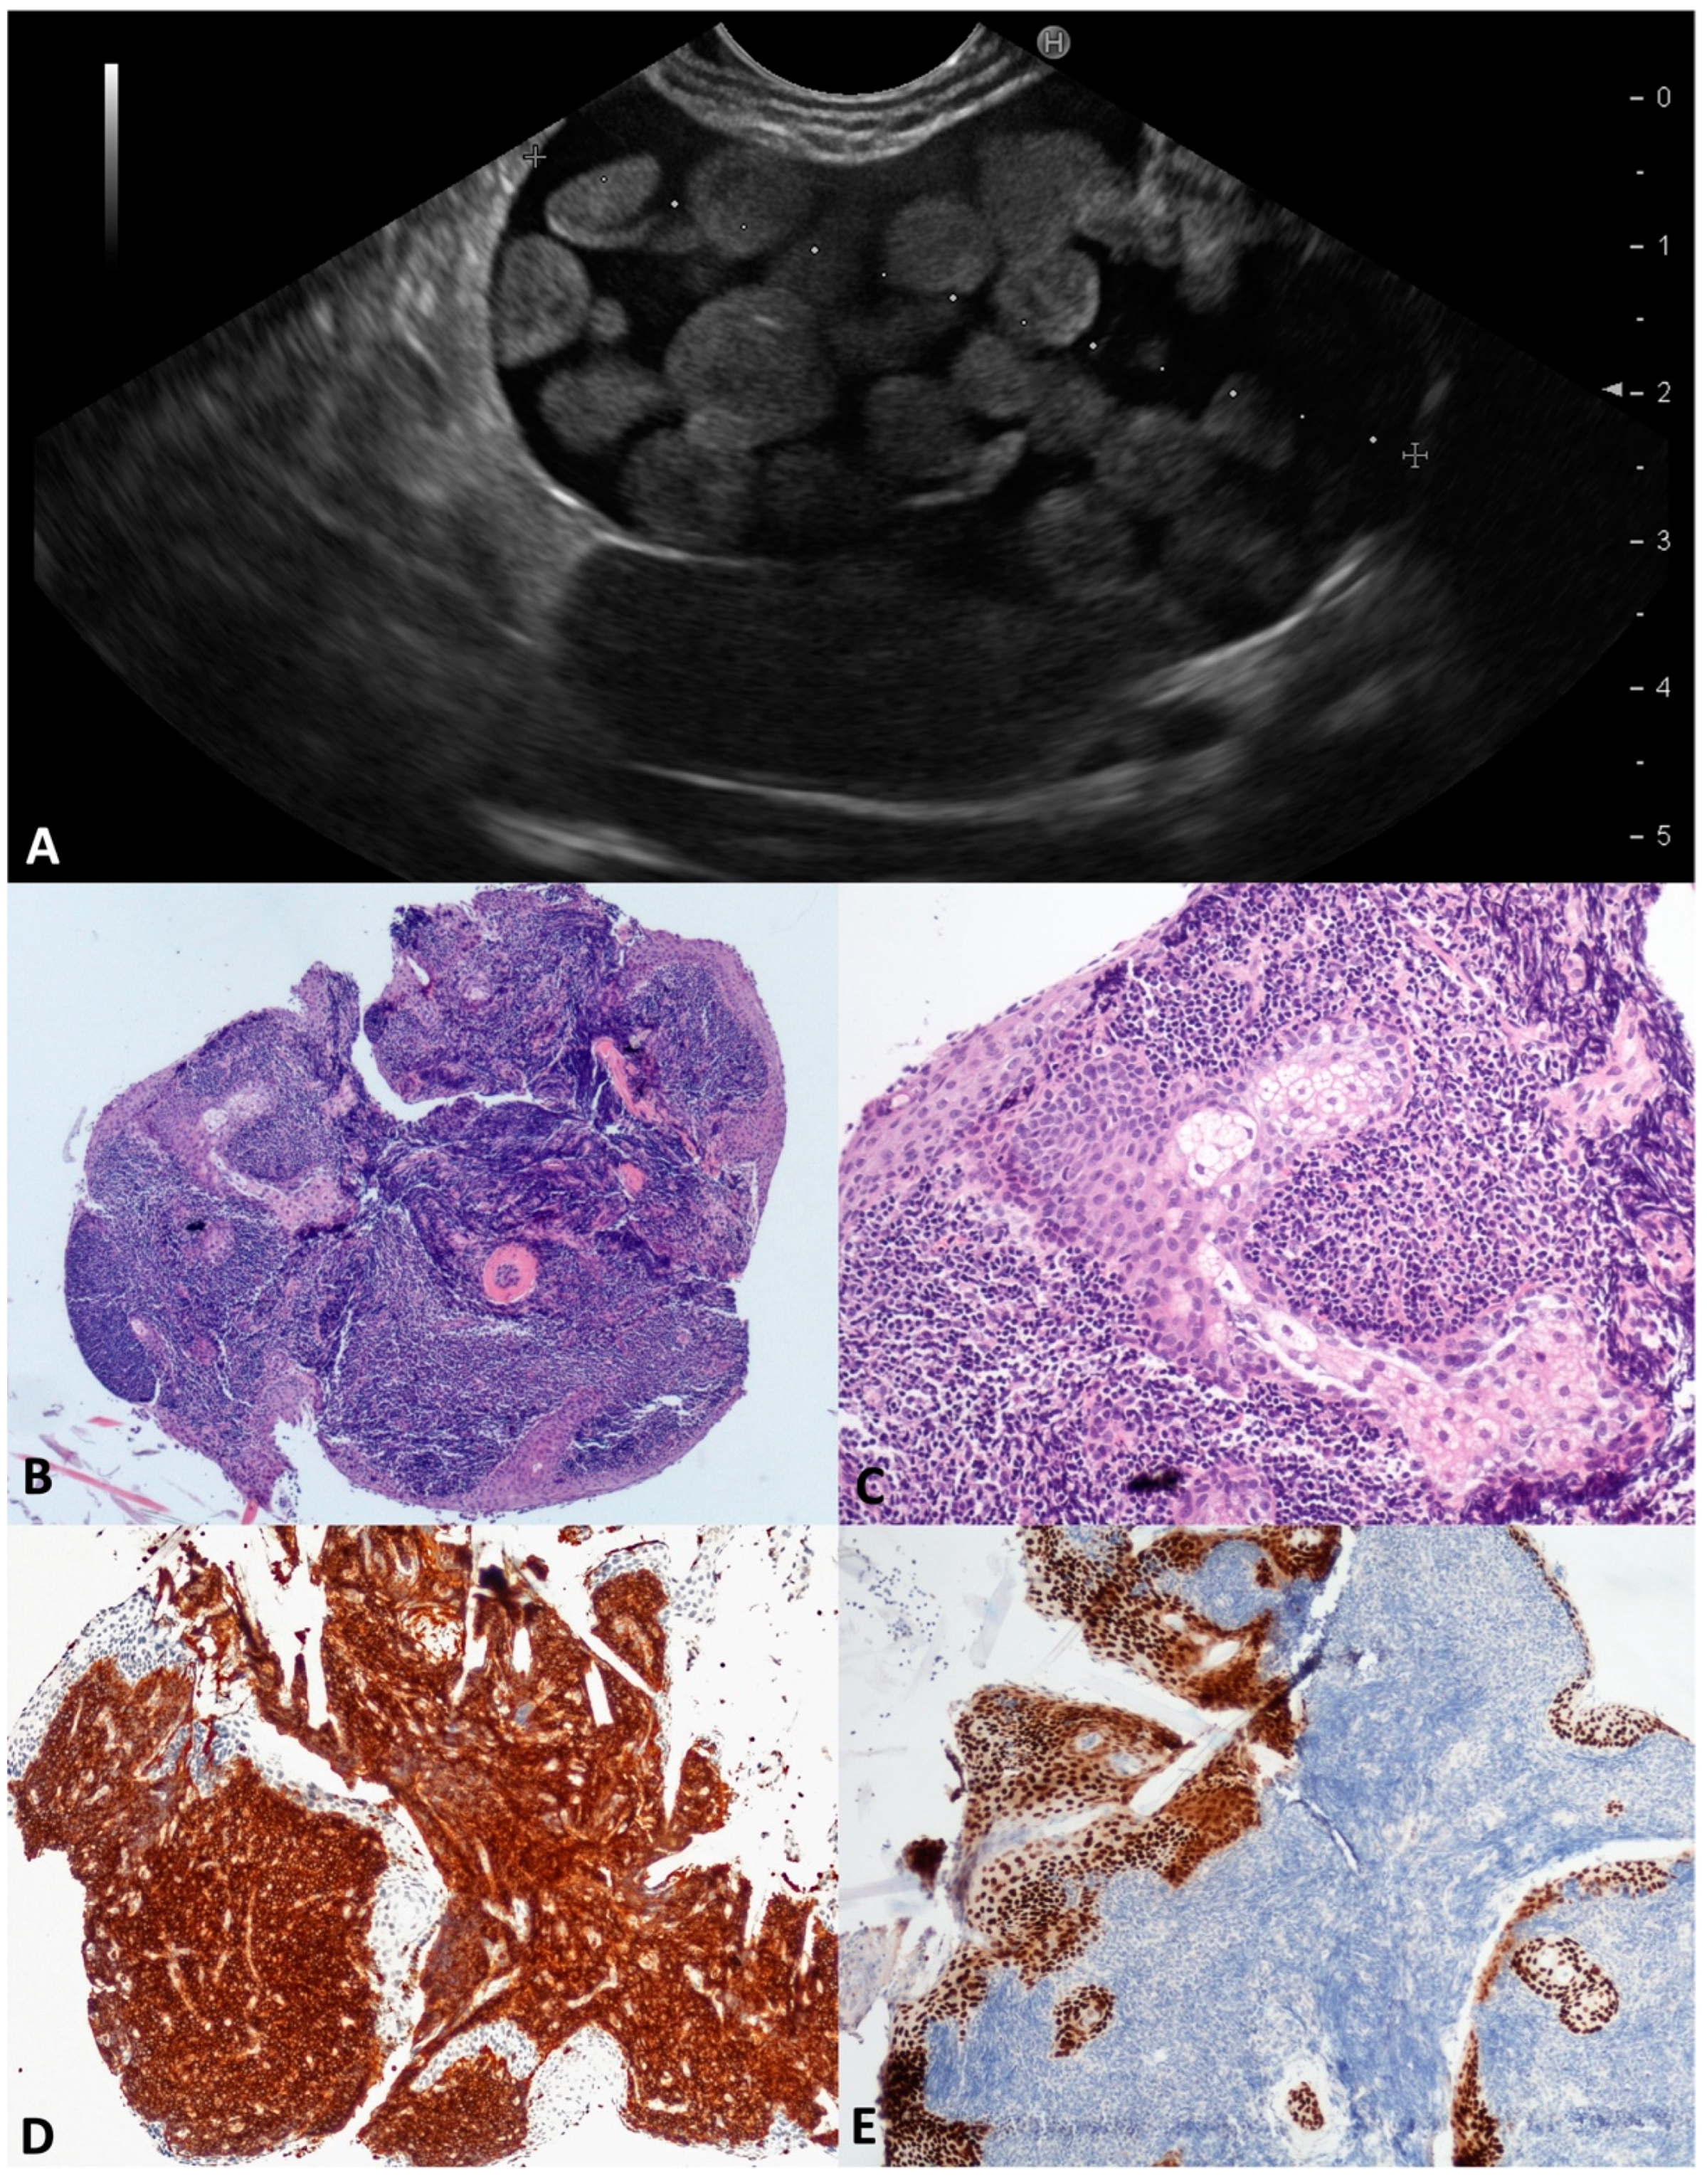

Pancreatic CLs are extremely uncommon (0.2% of PCLs), affecting typically young women; their growth is positively influenced by hormones (contraceptive, pregnancy, hyperprogesteronemia). Probably due to the progressive dilation of lymphatic vessels caused by insufficient drainage [], CLs usually present as large and well-defined multicystic lesions with a thin septa, and less frequently have a unilocular or oligocystic appearance (Figure 5A). The intracystic viscous fluid seems chilous in the FNA, due to the triglycerides content [,] (Figure 5B). In our series, four middle-aged patients (three males) presented with a large cyst (mean size 60 mm) at different locations within the pancreas. In two out of four (50.0%) patients, no definitive characteristics of CLs were preoperatively found, either in the fluid cytology or TTNB specimens, and the diagnosis was reached after surgery. According to the microscopy, the two TTNB diagnostic specimens were composed of smooth muscle bundles and collagenous fibers interposed between slit-like vascular spaces lined by a flat endothelium; the D2-40 and CD31 immunolabelling was positive. Focally, small aggregates of lymphocytes were identified in the collagenous tissue (Figure 5C–F).

Figure 5.

Cystic lymphangioma. Endoscopic ultrasound revealed an irregularly shaped multilocular cyst close to the pancreatic parenchyma, with a thin wall and septa (A). The aspirated fluid appeared as thick “milky” white-yellowish fluid (B). Numerous narrow lymphatic vessels lined by a cuboidal epithelium were separated by bundles of smooth muscle with few aggregates of lymphocytes (C). Immunolabelling for endothelial markers D2-40 (D) and CD31 (E). Bundles of smooth muscle actin (SMA) positive cells (F). Hematoxylin–eosin original magnification ×100 (C); D2-40 original magnification ×200 (D); CD31 original magnification ×200 (E); SMA original magnification ×200 (F).

In this series, two 60-year-old males were found to be affected by large (48 and 60 mm) LECs; these had a unilocular and oligocystic appearance, were thin-walled and located in the pancreatic body, and had an inhomogeneous content, in one case assuming a “floating balls” appearance (Figure 6A) due to the sebaceous glands inside. The aspirated intracystic fluid was yellow-brown and thick, with rare squamous cells in a background of amorphous material. According to the microscopy, the TTNB specimen was largely composed of aggregates of mature lymphocytes lined by a squamous keratinizing epithelium, with sebaceous glands associated (Figure 6B–E). No surgery was performed, and both patients were followed for a mean time of 36 months without clinical/morphological changes.

Figure 6.

Lymphoepithelial cyst. During the endoscopic ultrasound, a large cystic lesion with a regular wall and central thickened septum containing multiple round, echoic, and avascular floating balls after contrast injection was documented (A). The whole mounted section of the cyst wall forceps biopsy (B). Large aggregates of lymphoid cells are separated by squamous epithelial cells with sebaceous glands (C). Lymphocytes are highlighted by CD45 (D) and squamous cells by P63 (E) immunostaining, respectively. Hematoxylin–eosin original magnification ×40 (B), ×200 (C); CD45 original magnification ×100 (D); P63 original magnification ×100 (E).